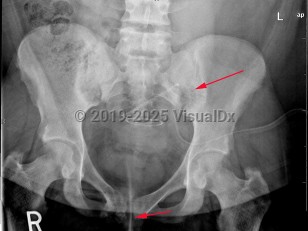

Patients are usually asymptomatic. Asymptomatic patients with incidentally discovered PHPT may have measurable end-organ manifestations, such as nephrocalcinosis, hypercalciuria, decreased cortical bone mineral density, and reduced creatinine clearance. Symptomatic patients have variable presentations. In mild cases, common symptoms include fatigue, lethargy, depression, muscle weakness, and muscle pain. In severe cases, symptoms include anorexia, nausea, vomiting, constipation, confusion, memory impairment, frequent urination, and bone thinning and fractures. Sustained hyperparathyroidism can lead to osteitis fibrosa cystica, forming cystlike tumors in the bones.